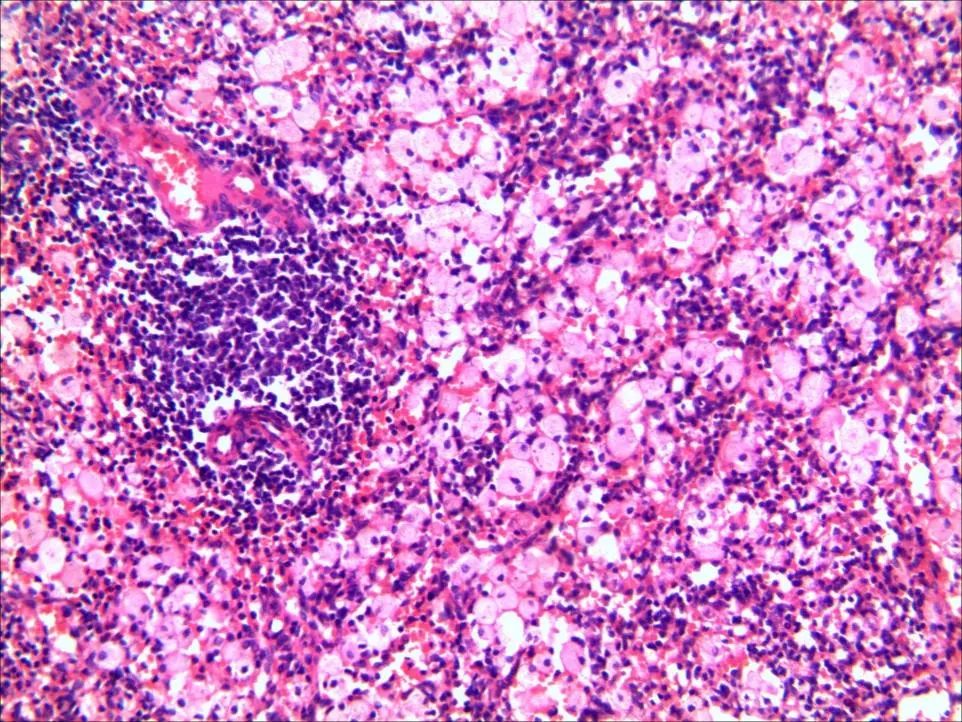

为明确脾大、脾亢原因,进一步行骨髓穿刺术,骨髓穿刺涂片:①全片可见较多海蓝组织细胞;②巨核细胞计数增多,产板巨核细胞减少,全片血小板成小堆可见;③嗜酸性粒细胞比例偏高占5.5%。骨髓活检:骨髓组织增生活跃,有核细胞容量约50%;粒系、红系比例正常;巨核系细胞0~1个/HPF,形态正常(图2)。

图2. 骨穿:骨髓组织增生活跃,有核细胞容量约50%;粒系、红系比例正常;巨核系细胞0~1个/HPF,形态正常

患者脾大显著,可压迫胃肠道,导致腹胀;牙龈出血行凝血机制正常,牙龈检查未见充血肿胀,骨髓穿刺未见血友病,白血病等血液系统疾病导致牙龈出血可能,考虑血小板减少导致牙龈出血;诊断为:原发性血小板减少性紫癜,海蓝组织细胞增生症;于2014年7月8日行脾切除术,术后脾脏病理:免疫组织化学及特殊染色结果考虑蜡样质组织细胞增生症(成人型Niemann-Pick病)(图3)。

图3. 脾脏:脾脏白髓萎缩,红髓扩大,脾索内可见大量海蓝组织细胞聚集,海蓝组织细胞呈嗜碱性空泡状胞质